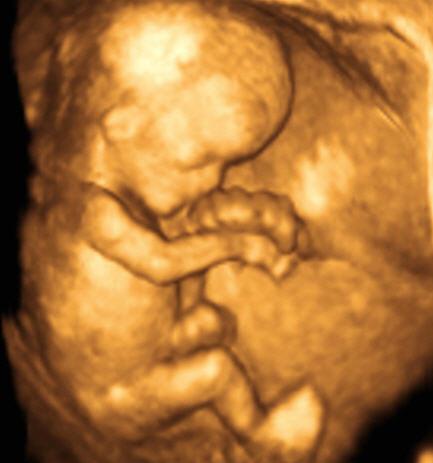

2nd trimester ultrasound

It enables :

• Study the morphology of the fetus and its organs

• Check for malformations

• Determine fetal growth and well-being

• Determine the location of the placenta.